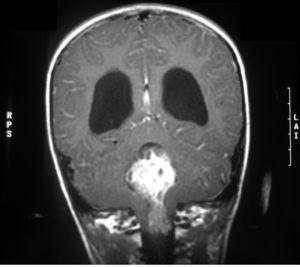

La tomografía computarizada (TC) cerebral con contraste mostraba una tumoración en el techo del cuarto ventrículo con calcificaciones, edema perilesional e hidrocefalia triventricular (fig. 1). Las resonancias magnéticas (RM) cerebral y de neuroeje con gadolinio confirma la presencia de la tumoración con una alta sospecha de ependimoma (fig. 2).

Figura 2.RM craneal coronal con gadolinio al diagnóstico. Tumoración de 3 cm de diámetro mayor, localizada en el cuarto ventrículo que desciende a través del agujero de Majendi, y que provoca una hidrocefalia obstructiva activa. Sospecha de ependimoma.